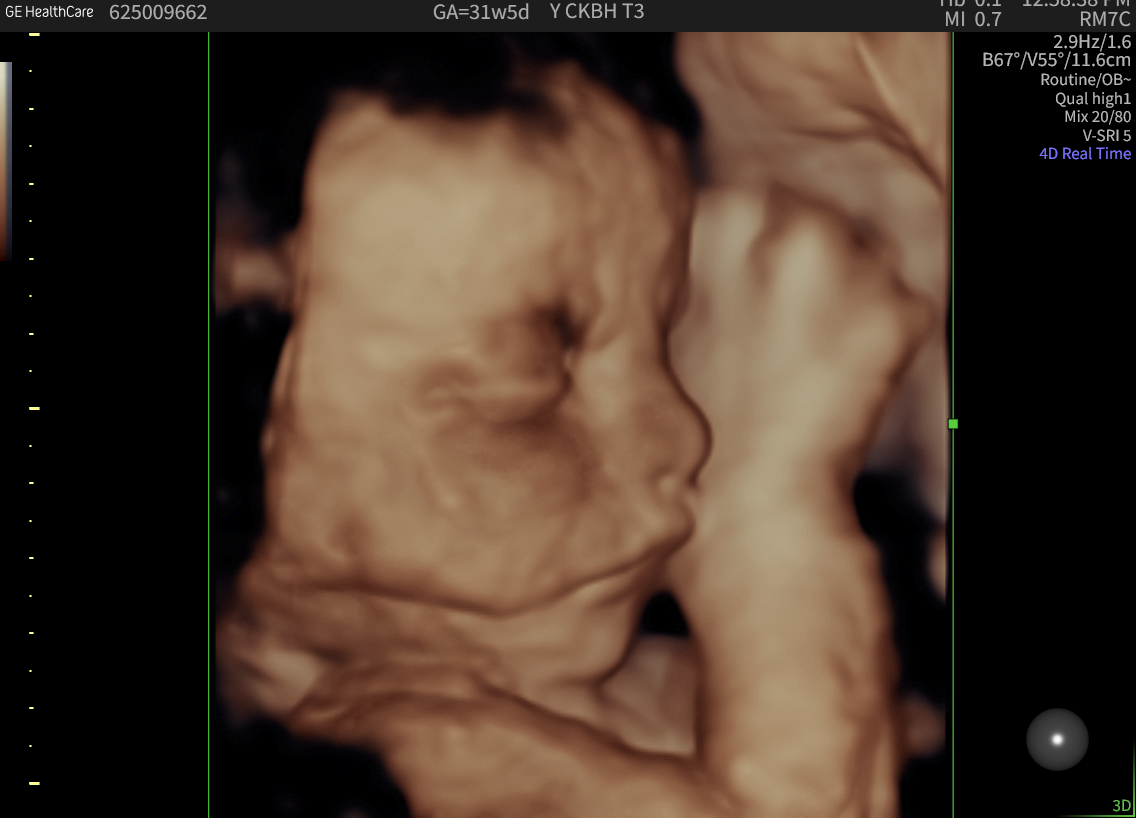

In ‘2D’ ultrasound, only a thin slice of the fetus is viewed at any one instant. This allows a lot of detail, and the person performing the ultrasound (the sonographer) mentally gets the third dimension by moving the probe. With 3D ultrasound, a whole series of slices are taken in quick succession. The slices are then put together to look more like a picture you would see with your eyes. To get the rapid multiple slices, each individual ultrasound slice contains diluted information.

4D is a description of 3D that tells you it is being performed live. Therefore, the fetal movement is seen.

The quality of 3D and 4D images depends on several factors, including the baby’s position, the amount of fluid around the face, and whether limbs or the umbilical cord are blocking the view. As with 2D ultrasounds, maternal build can also influence the image quality.

When the conditions are right, seeing your baby’s face in 3D can be an unforgettable experience for parents-to-be. However, it’s good to keep in mind that some minor distortions are a natural part of the imaging process.